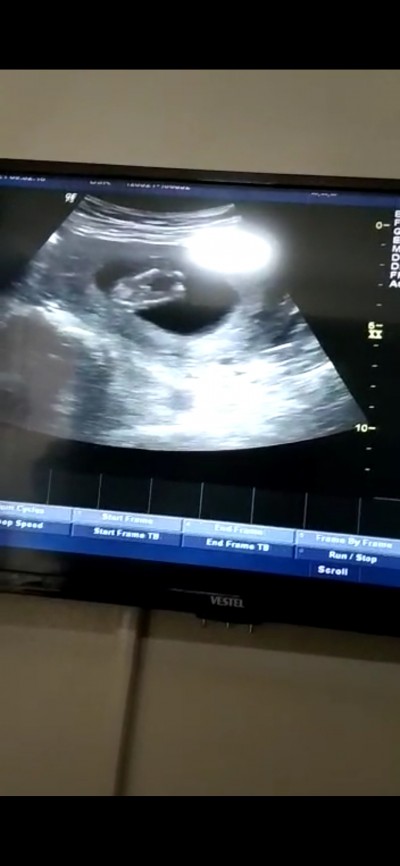

Kızlar bugün 14+1 de cinsiyetimizi öğrendik  öyle bir poz verdiki yaramaz çok mutluyum. Belki göstermez diye gittim oğlum oluyor hayırlısı ile gelsin